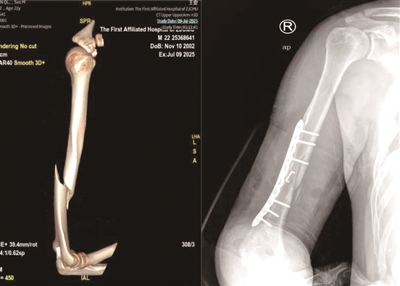

阿琦断裂的肱骨

今年暑假,22岁大学生阿琦和朋友开心聚餐。酒过三巡,气氛正嗨,阿琦向朋友小邢提议“掰手腕”。两人开始对决,双臂紧锁,青筋暴起,突然一声清脆的“咔嚓”声响起,阿琦右臂剧痛,冷汗直流。朋友们赶紧把他送到浙江省中医院钱塘院区,经检查“右肱骨干骨折,合并桡神经损伤”。

2021年3月的一天,30岁的小马在街边烧烤摊和朋友小聚。酒过三巡和朋友“掰手腕”比力气,小马猛然发力,忽然“咔嚓”一声右臂剧痛,动弹不得。送到杭州市一医院急诊,X光片显示“肱骨干断裂”,断掉的肱骨好似麻花一样,呈现螺旋形状。

浙江省中医院骨伤科医生李飞说,掰手腕时,手臂肌肉会瞬间爆发出强大的收缩力,这股力量沿着上臂骨骼(肱骨)传导,肱骨中下段就像一根筷子最容易被掰断的位置,非常不耐“扭转”和“剪切”。当姿势不当,强大的力量持续对抗时,肱骨就可能像被硬生生掰断的树枝一样,发生螺旋形骨折。